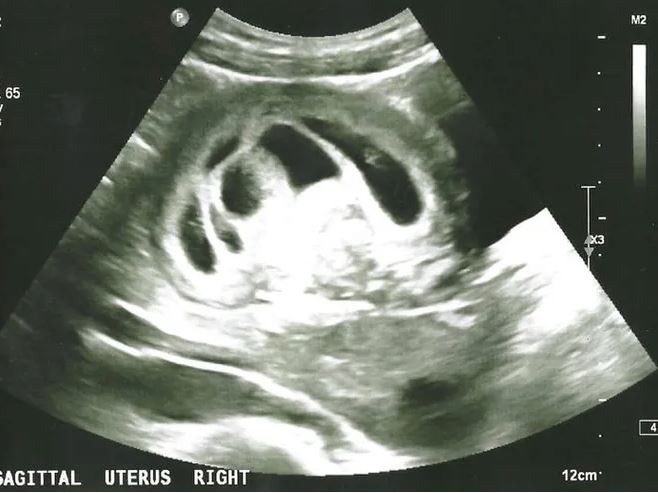

По результатам УЗИ в восемь недель беременности у Лиззи обнаружили семь плодов – шесть жизнеспособных и один замерший. Врачи видели два сценария развития событий: женщина могла продолжить вынашивать беременность с 50% вероятностью гибели всех эмбрионов, полностью прервать беременность или пройти процедуру селективного аборта, в результате которого в матке остается один или два плодных яйца, но повышается риск самопроизвольного выкидыша.